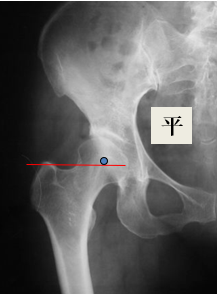

偏心距(Offset)股骨偏心距:股骨头中心到股骨纵轴的垂直距离外展肌的动力臂

髋关节的偏心距(Hip Offset)

-髋关节偏心距 ≠ 股骨偏心距

-关注髋臼(臼杯)偏心距acetabular or cup offset,AO